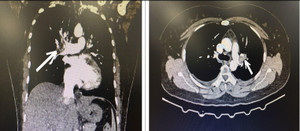

Trước đó, đêm 17/10, nam bệnh nhân 52 tuổi (ngụ Hóc Môn, TP.HCM) nhập viện cấp cứu Bệnh viện Nhân dân Gia Định trong tình trạng đau ngực dữ dội. Bệnh nhân được chẩn đoán nhồi máu cơ tim do tắc hoàn toàn động mạch vành phải.

TS.BS Bùi Minh Thành, Trưởng khoa phẫu thuật Tim, Bệnh viện Nhân dân Gia Định nhận định, đây là trường hợp nặng, tuy bệnh nhân còn trẻ, nhưng hẹp và tắc nhiều nhánh chính động mạch vành, mắc một số bệnh nền và có thể nhồi máu cơ tim tái phát.

Ngày 2/11, bệnh nhân được phẫu thuật. Quá trình gây mê diễn ra thuận lợi. Tuy nhiên, khi vừa kết thúc công đoạn lấy một đoạn tĩnh mạch dưới chân để làm cầu nối thì đột nhiên huyết áp tụt nhanh và bệnh nhân ngưng tim. Sau khi xử lý, tình trạng ngừng tim vẫn không đáp ứng. Bác sĩ quyết định mở ngực ngay bằng cưa xương ức, mở màng ngoài tim để có thể xoa bóp tim trực tiếp, đồng thời thực hiện các mũi khâu trên động mạch chủ và trên tim để khởi động tuần hoàn ngoài cơ thể nhanh nhất có thể.

Theo TS.BS Bùi Minh Thành, nhồi máu cơ tim gây biến chứng vỡ tim gặp từ 5 -10% trường hợp nhồi máu cơ tim cấp, thường xảy ra trong khoảng hai tuần sau nhồi máu và thông thường gây đột tử. Trường hợp vỡ tim là tình huống này xảy ra bất ngờ trong phòng mổ.